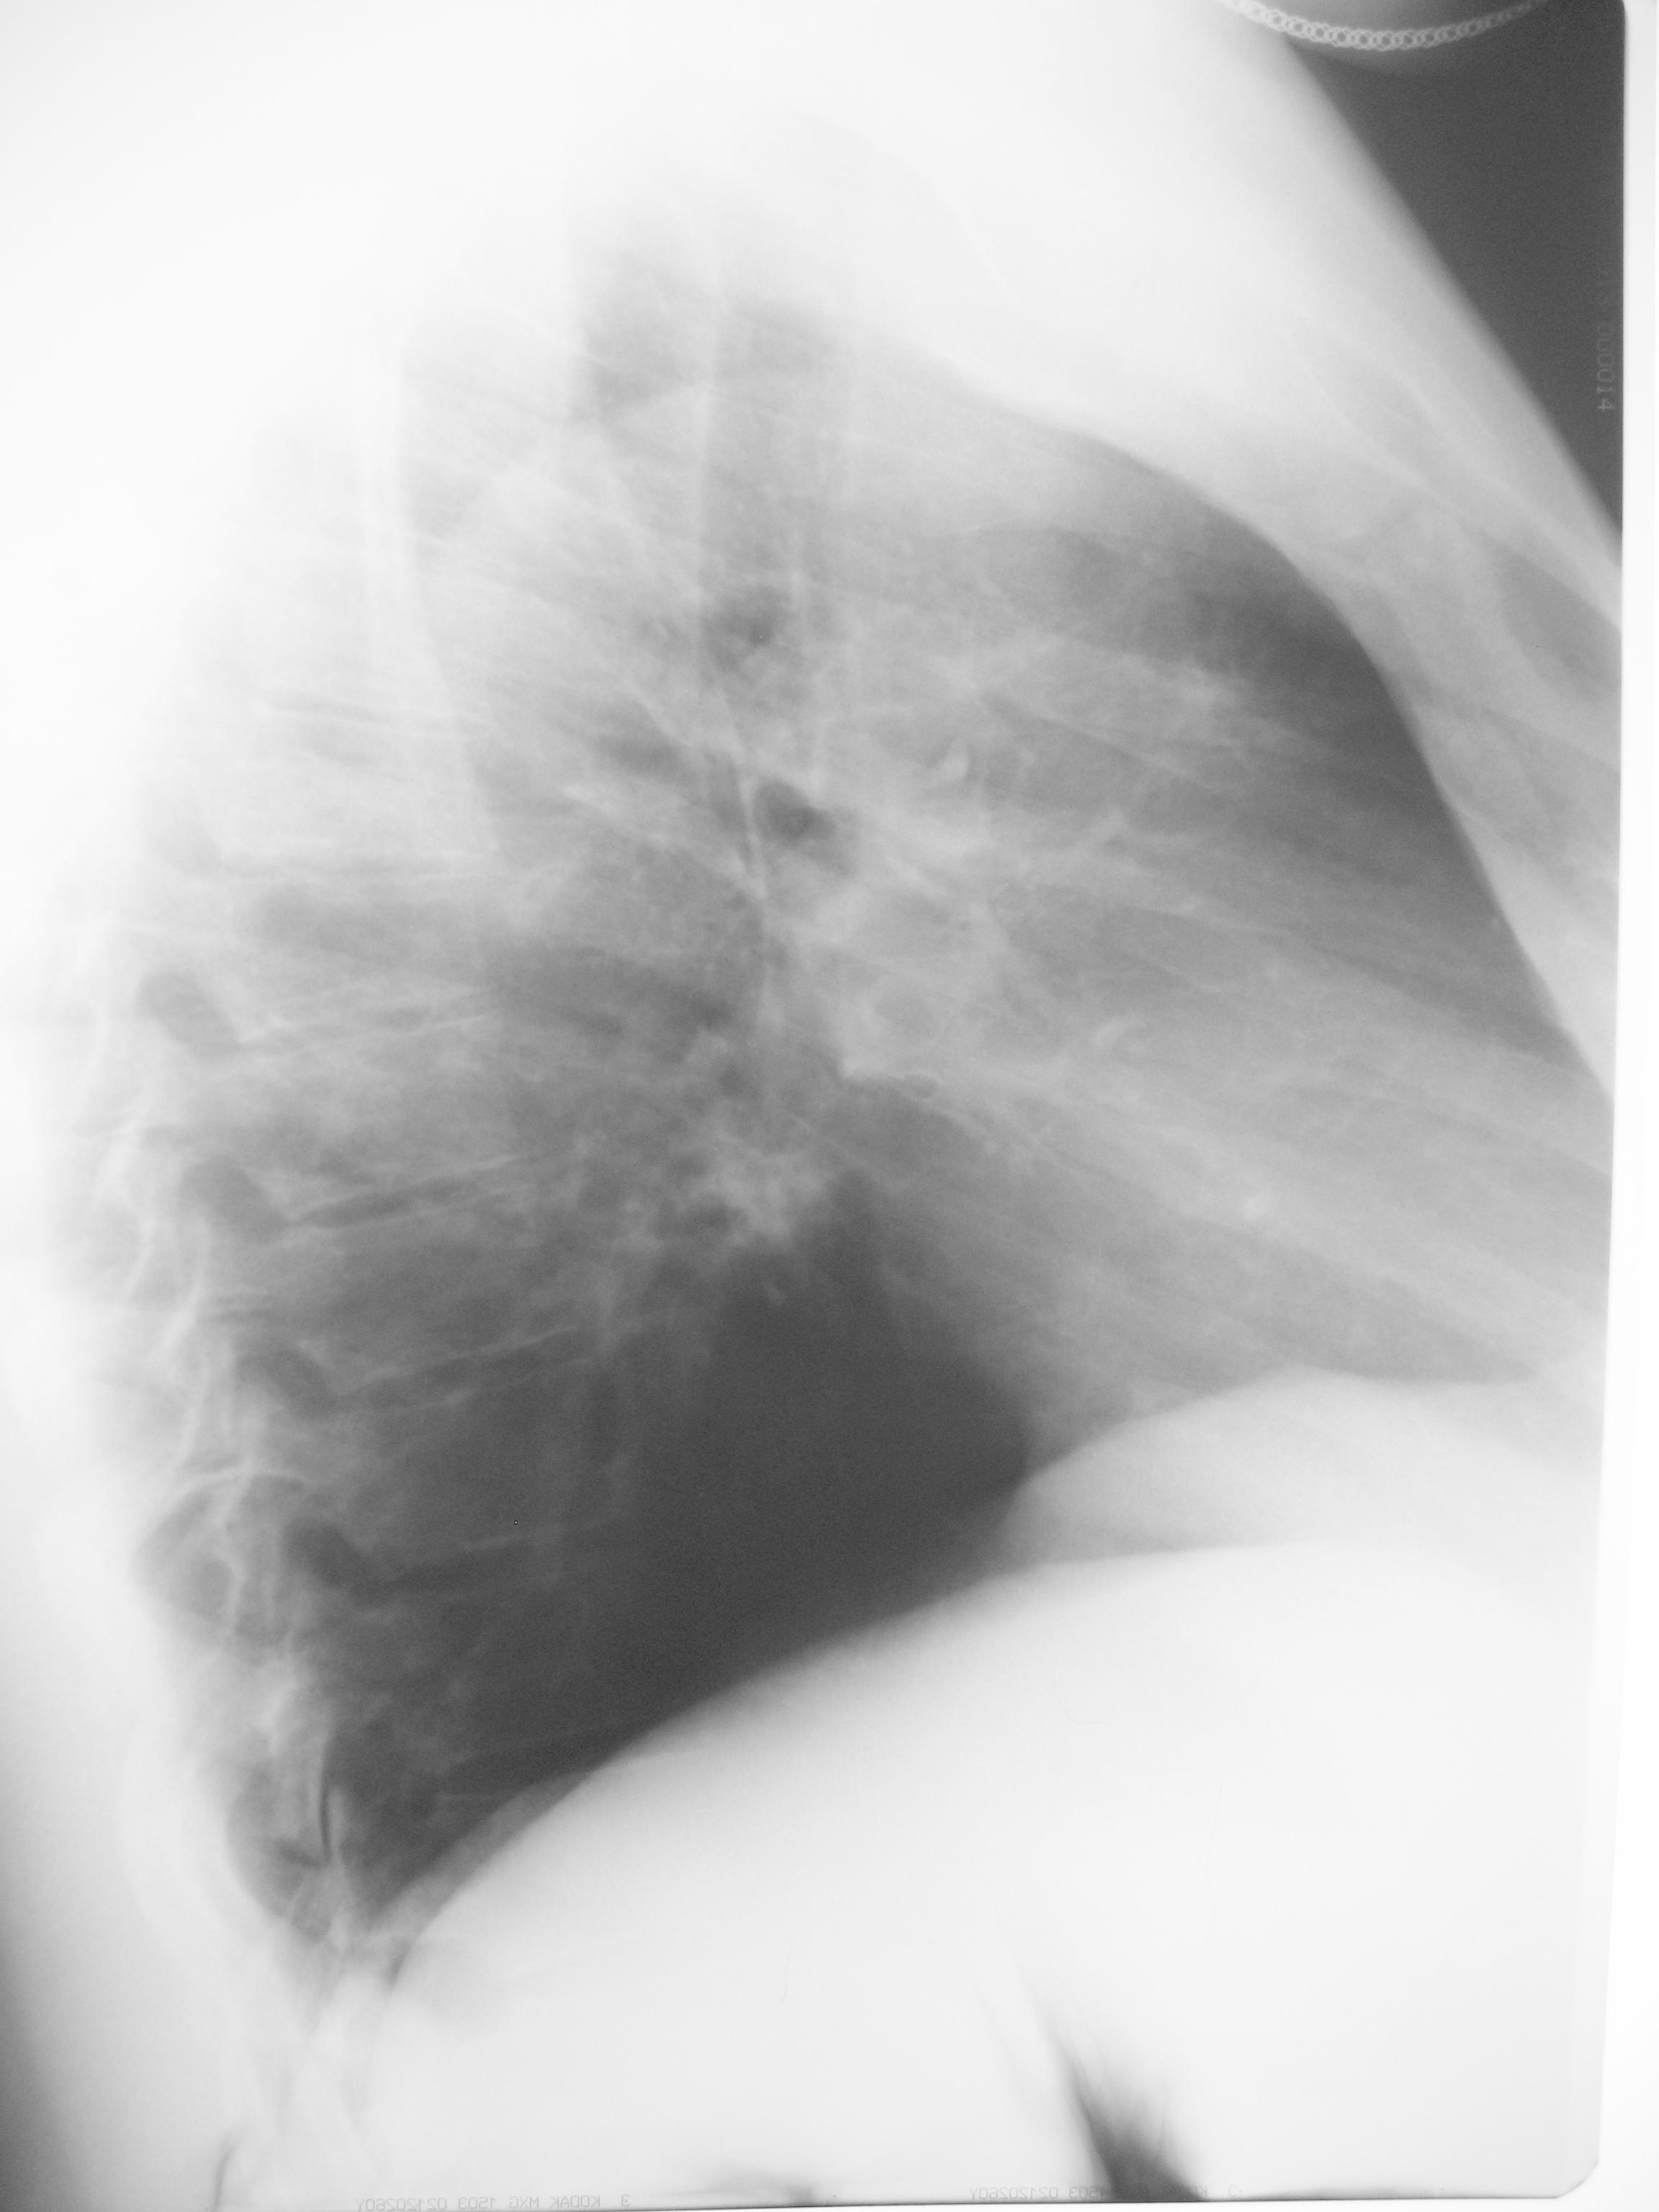

В поликлинике у нас томографии нет, КТ через пульмонолога в др учредении. Все же, похоже ли на тбс и какой очаговый (но тени больше 1 см) или инфильтративный? А нижняя тень по моему не в 8 сегменте, а выше быть должна на боковом, если ориентироваться по прямому

согласна с данным мнением, правый корень не реагирует, при твс должен, и локализация - S8, S3 без старого твс архива редко при твс, конечно, могу ошибаться, как все, но склоняюсь к мнению периферического с-ч правого легкого с внутриорганным мтс.

Дайком тяжеловат, выложила срезы с наибольшими изменениями в легких.

. Просто какая-то эпидемия саркоидоза настала ! Похоже, теперь в ДДЗ пневмонии и ТВС надо будет всем писать и саркоидоз

Тут вроде бы саркоидоз под вопросом, если бы кто взялся посмотреть, можно постараться весь дайком выложить.